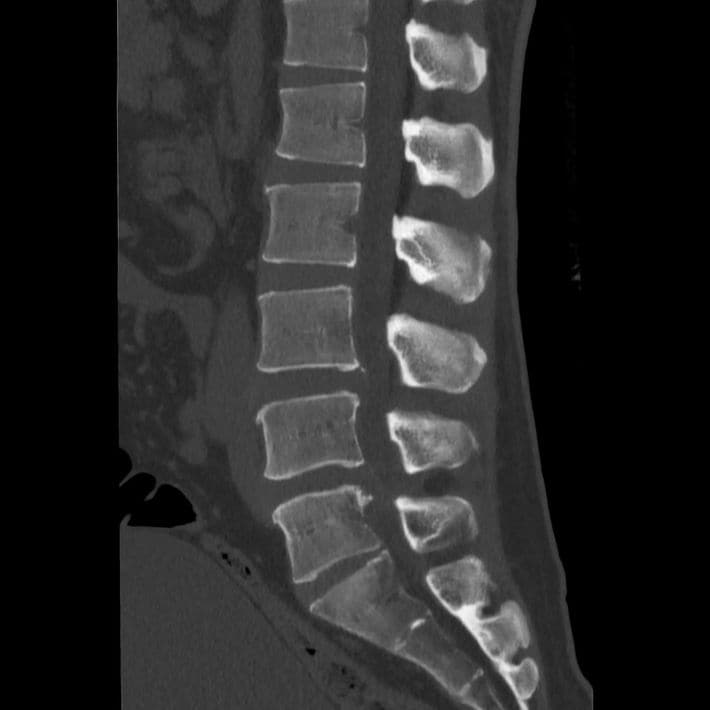

一般的に骨の形や配列、変形を詳しく調べるためCTを撮影する。この画像では一部に腰痛の原因となる可能性がある所見が認められた。(『

カニジル 18杯目

』より)